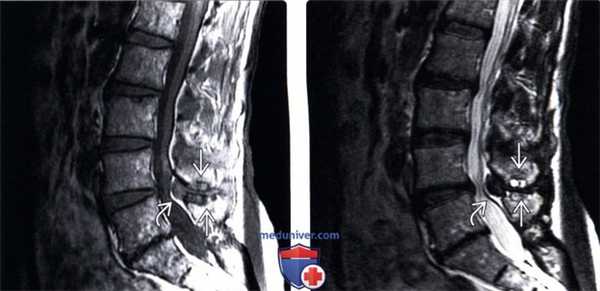

(Слева) Т1-ВИ, сагиттальная проекция: неровность контуров обращенных друг к другу краев остистых отростков L4 и L5 в классическом сочетании с гипертрофией желтой и межостистой связок.

(Справа) Т2-ВИ, сагиттальный срез: классическая картина болезни Бааструпа в виде кистозной дегенерации соприкасающихся поверхностей остистых отростков, определяемой в виде фокусов усиления сигнала. Видны признаки выраженной гипертрофии желтой связки, а также тяжелого дегенеративного поражения дугоотростчатых суставов.

(Слева) STIR МР-И, сагиттальная проекция: случай болезни Бааструпа, выраженной в виде неправильной формы участка усиления сигнала межостистой связки L2-L3. В дорзальном отделе эпидурального пространства видна синовиальная (юкстаартикулярная) киста с белковым содержимым (снижение интенсивности сигнала в центральной зоне), вызывающая значимый стеноз спинномозгового канала.

(Справа) Т2-ВИ, сагиттальная проекция: признаки болезни Бааструпа в виде нечеткости контуров межостистой связки и изменения формы кортикальных пластинок смежных остистых отростков. Обратите внимание на наличие также эпидуральной кисты с белковым содержимым.